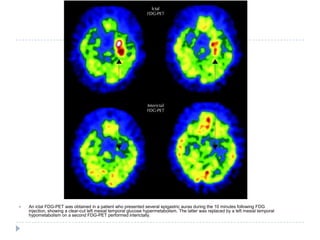

An ictal FDG-PET was obtained in a patient who presented several epigastric auras during the 10 minutes following FDG injection, showing a clear-cut left mesial temporal glucose hypermetabolism. The latter was replaced by a left mesial temporal hypometabolism on a second FDG-PET performed interictally.

An ictal FDG-PETwas obtained in a patient who presented several epigastric auras during the 10 minutes following FDG injection, showing a clear-cut left mesial temporal glucose hypermetabolism. The latter was replaced by a left mesial temporal hypometabolism on a second FDG-PET performed interictally.